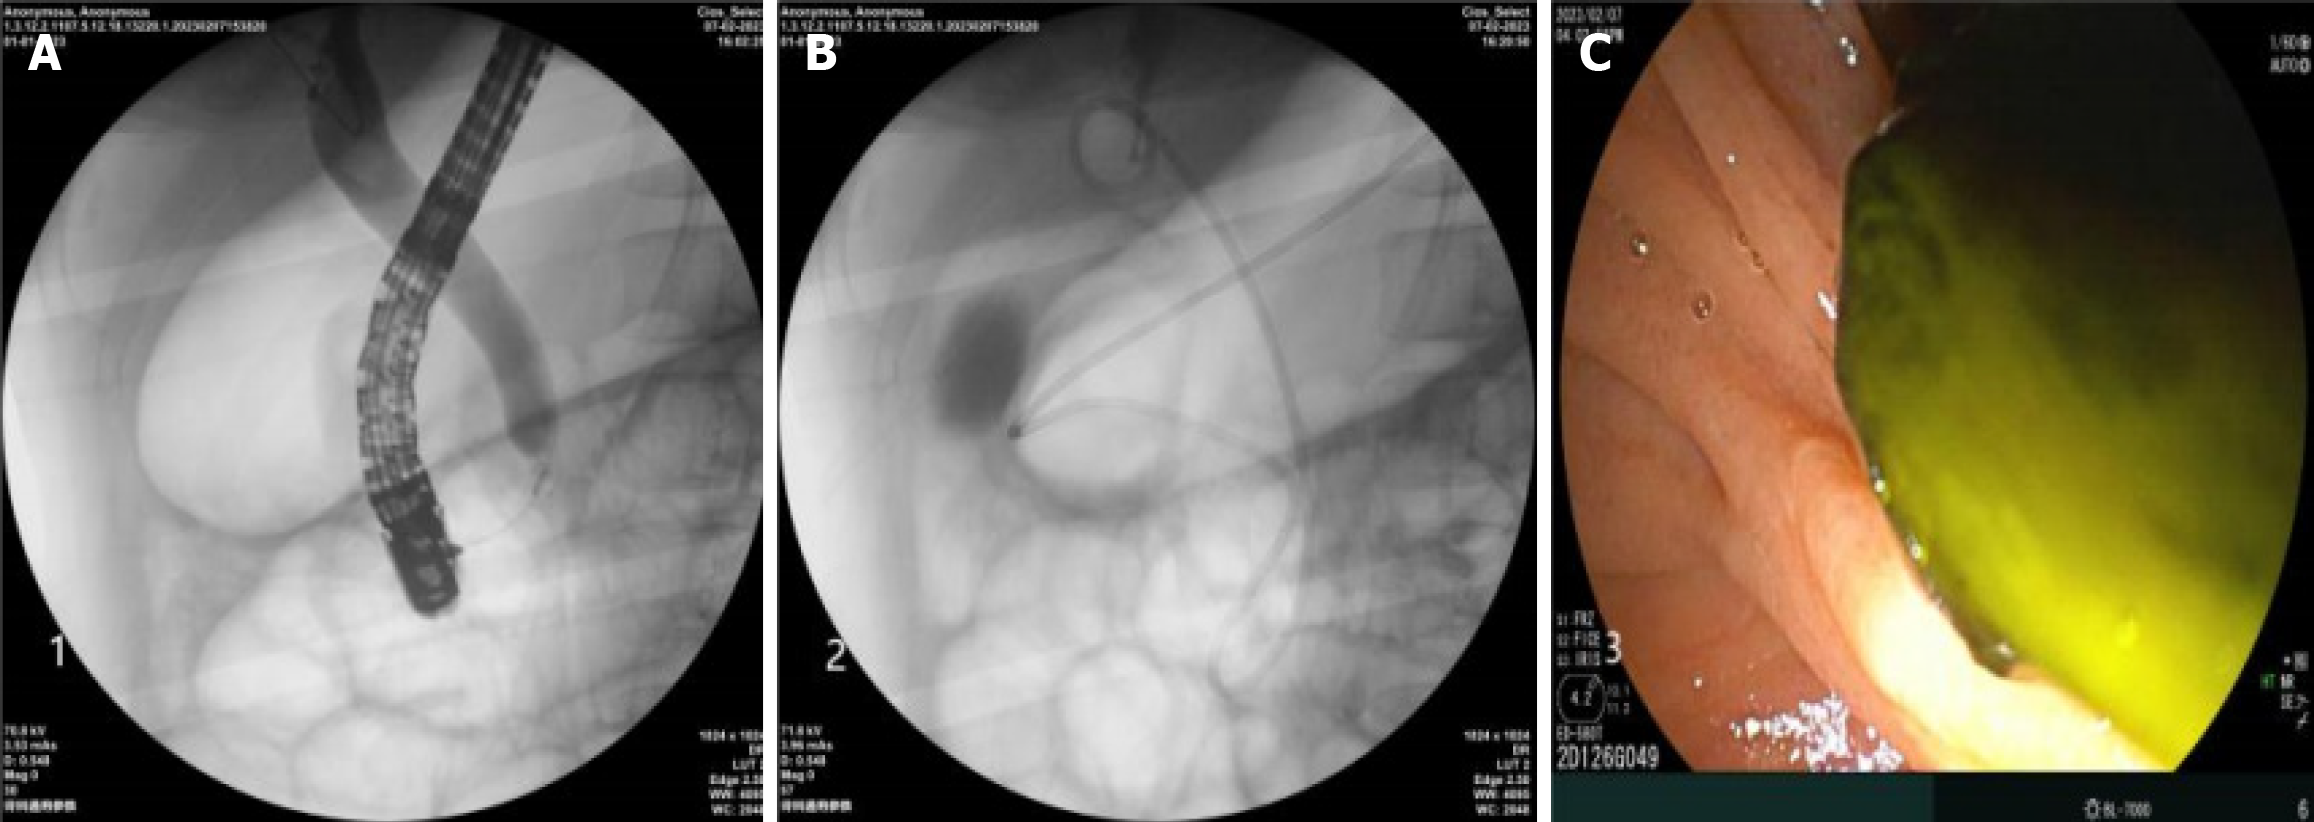

After a definitive diagnosis, appropriate treatment was implemented based on the findings. For patients with confirmed common bile duct stones, stone extraction was performed using a balloon catheter or basket to either trap or retrieve the stone. If stone removal was difficult, EST or EPBD was performed to enlarge the papillary opening. Stone removal was then attempted again using the same method. After stone removal, an endoscopic nasobiliary drainage tube was placed for external drainage, or a plastic biliary stent (endoscopic retrograde biliary drainage) was inserted for internal drainage. For patients diagnosed with common bile duct cysts, biliary infections, pancreatic divisum syndrome, or acute/chronic pancreatitis, corresponding measures were taken intraoperatively, including biliary drainage, pancreatic duct stent insertion, and nasopancreatic tube placement, to ensure smooth pancreatic and biliary drainage. After ERCP, the endoscope was removed, and after recovery, the child was returned to the ward. Postoperative fasting was maintained for 6-8 hours, and symptomatic supportive treatment such as fluid resuscitation, anti-infection, and enzyme inhibition was provided. Close monitoring of abdominal pain, body temperature, amylase, and bilirubin levels was performed to prevent postoperative complications such as pancreatitis, perforation, bleeding, or infection. The entire ERCP procedure emphasized precise understanding of pediatric pancreatobiliary anatomy and the principle of minimal trauma. Figure 1 shows the typical steps of ERCP for common bile duct stones.